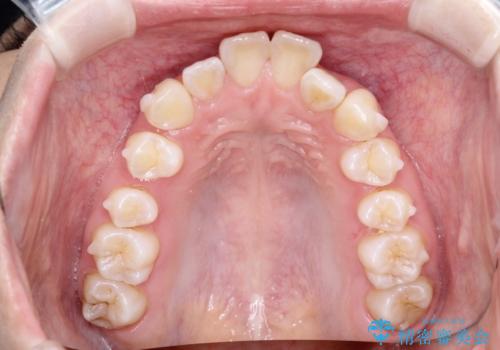

- 初診時には上顎前歯の突出、前歯部の深いかみ合わせ、叢生が見られる状態でした。

インビザラインにて不正咬合の原因除去を行うシミュレーションを念入りに制作の上、治療を行いました。